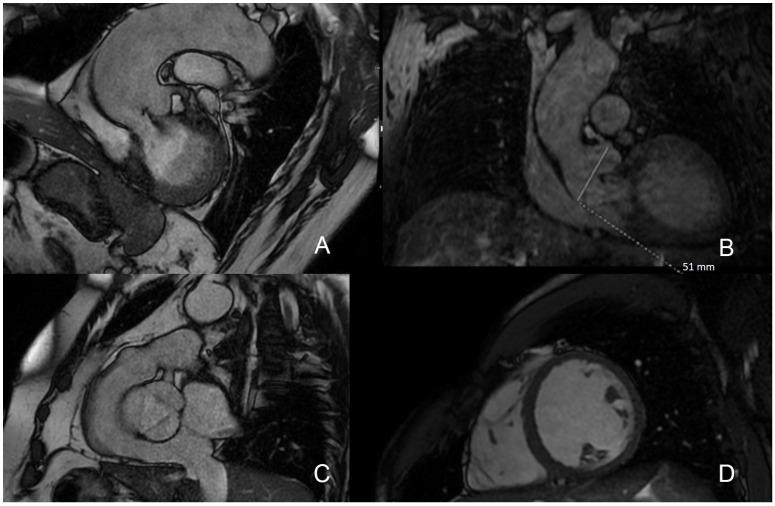

心脏磁共振在主动脉瓣狭窄和反流中的作用。

The Role of Cardiac Magnetic Resonance in Aortic Stenosis and Regurgitation.

Cardiac magnetic resonance (CMR) imaging is a well-set diagnostic technique for assessment of valvular heart diseases and is gaining ground in current clinical practice. It provides high-quality images without the administration of ionizing radiation and occasionally without the need of contrast agents. It offers the unique possibility of a comprehensive stand-alone assessment of the heart including biventricular function, left ventricle remodeling, myocardial fibrosis, and associated valvulopathies. CMR is the recognized reference for the quantification of ventricular volumes, mass, and function. A particular strength is the ability to quantify flow, especially with new techniques which allow accurate measurement of stenosis and regurgitation. Furthermore, tissue mapping enables the visualization and quantification of structural changes in the myocardium. In this way, CMR has the potential to yield important prognostic information predicting those patients who will progress to surgery and impact outcomes. In this review, the fundamentals of CMR in assessment of aortic valve diseases (AVD) are described, together with its strengths and weaknesses. This state-of-the-art review provides an updated overview of CMR potentials in all AVD issues, including valve anatomy, flow quantification, ventricular volumes and function, and tissue characterization.

摘要

心脏磁共振(CMR)成像对于评估心脏瓣膜病是一种成熟的诊断技术,并且在当前临床实践中越来越受到重视。它无需电离辐射即可提供高质量图像,偶尔也无需使用造影剂。它提供了对心脏进行全面独立评估的独特可能性,包括双心室功能、左心室重塑、心肌纤维化以及相关瓣膜病变。CMR是公认的心室容积、质量和功能量化的参考标准。其一个特别优势是能够量化血流,尤其是采用允许精确测量狭窄和反流的新技术时。此外,组织成像能够实现心肌结构变化的可视化和量化。通过这种方式,CMR有潜力产生重要的预后信息,预测哪些患者将进展至手术并影响预后。在本综述中,将描述CMR评估主动脉瓣疾病(AVD)的基本原理及其优缺点。这篇前沿综述提供了CMR在所有AVD问题方面潜力的最新概述,包括瓣膜解剖、血流量化、心室容积和功能以及组织特征。